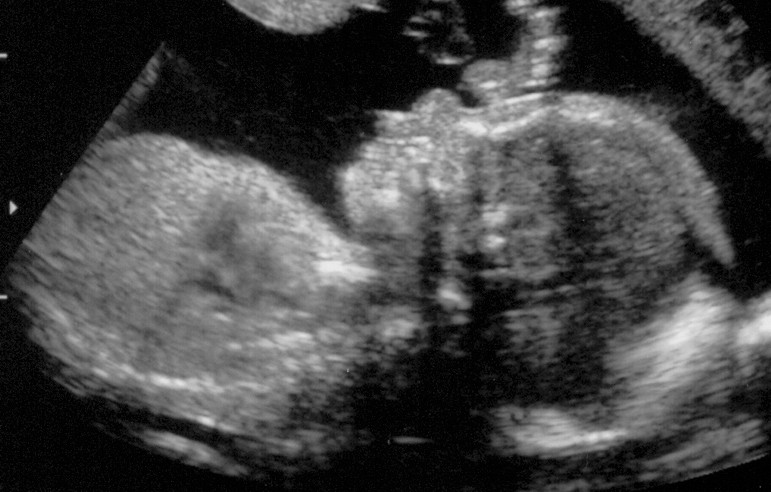

Linkes Kind im "normalen" US

Rechtes Kind im "normalen" US

Sorry, dass ich euch bis heute auf die Folter gespannt habe, aber: Nun hat das Warten hat ein Ende ES GIBT NEUE FOTOS!!!

Ist ja echt Wahnsinn, was heute technisch so alles machbar ist. Wir waren übrigens im Klinikum Kassel bei Dr. Simoens. Wenn die Möglichkeit besteht, kann ich das nur empfehlen. Die Wartezeit war extrem kurz und der Doc war sehr nett. Darüber hinaus hat er im Untersuchungszimmer zwei zusätzliche riesige Bildschirme damit sowohl Mann als auch Frau alles sehen können. Echt Klasse.

Hintergrund der Untersuchung war - so die normale Gyn - dass sie bei Mehrlingsschwangerschaften grundsätzlich ein Fehl-/Missbildungs-Sono machen lässt. Soweit es im US ersichtlich war, ist glücklicher Weise alles in Ordnung.